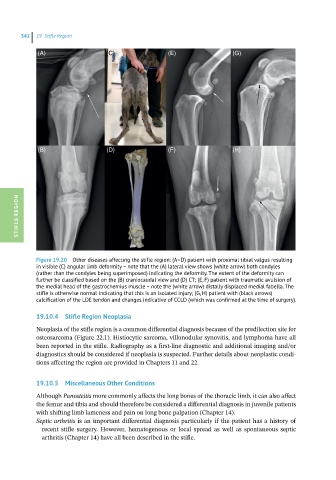

Figure 19.20 Other diseases affecting the stifle region: (A–D) patient with proximal tibial valgus resulting

in visible (C) angular limb deformity – note that the (A) lateral view shows (white arrow) both condyles

(rather than the condyles being superimposed) indicating the deformity. The extent of the deformity can

further be classified based on the (B) craniocaudal view and (D) CT; (E, F) patient with traumatic avulsion of

the medial head of the gastrocnemius muscle – note the (white arrow) distally displaced medial fabella. The

stifle is otherwise normal indicating that this is an isolated injury; (G, H) patient with (black arrows)

calcification of the LDE tendon and changes indicative of CCLD (which was confirmed at the time of surgery).